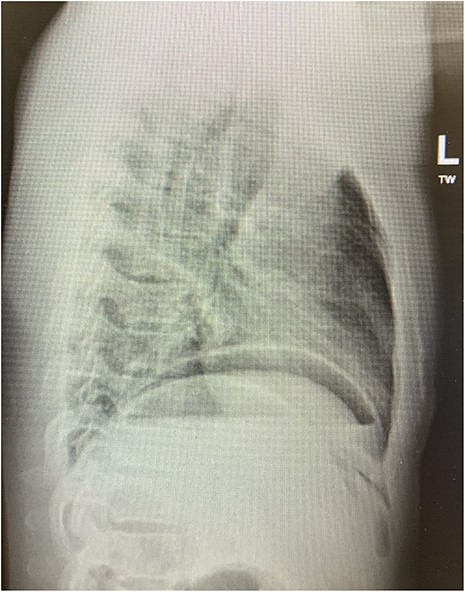

On examination in the emergency department, he was found to have localized peritonism to the epigastrium and was diaphoretic. An urgent erect chest radiograph (Figs 1 and 2) was revealing of gross pneumoperitoneum, presumably of a hollow viscous perforation as the source. General surgery was consulted after the presence of free air was detected. In the setting of the patient’s virgin abdomen and unremarkable surgical history, with peritonism and free intraperitoneal gas, the patient proceeded directly to urgent exploratory laparotomy with concurrent resuscitation measures, including intravenous fluid resuscitation and placement of an indwelling catheter.